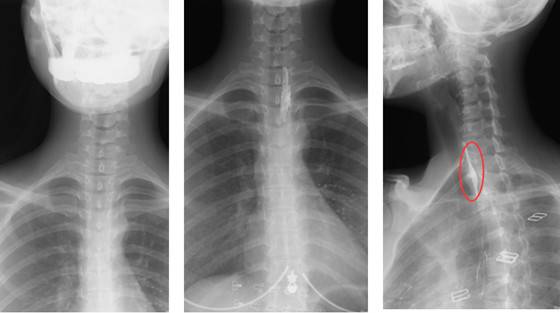

(2)消化道阴性异物

消化道阴性异物就是在X射线透视的情况下,无法显示的异物,这个异物不阻挡X射线,且能够透视X射线。

一个成人病人,吃了鱼骨卡在喉部,病理表现是嗓子痛、出血;通过用动态DR进行消化道吞钡棉检查,一口造影剂,一口棉花;如果鱼刺比较小,那么在钡棉经过的时候鱼刺就会挂在钡棉上,顺着造影剂流下去从而达到治疗的目的;如果鱼刺比较大,那么钡棉就会被挂在鱼刺上,停留在鱼刺所在位置;这时动态DR就可以进行定位,然后医生可以通过定位用胃镜或耳鼻喉镜将鱼刺取出来。这就是动态精准诊断或精准治疗的优势。